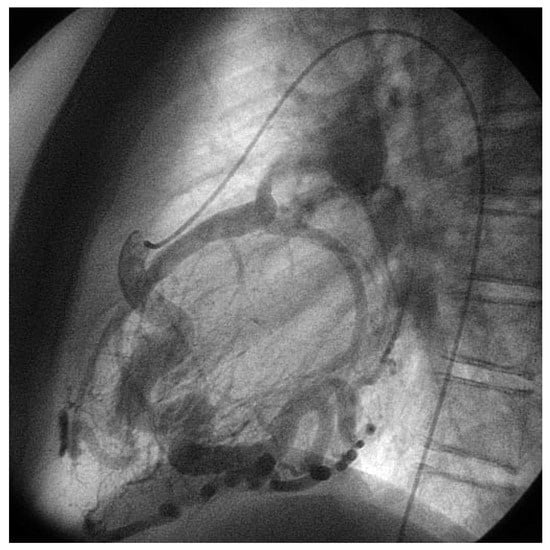

An otherwise healthy 13-year-old girl was referred to the pediatric cardiology outpatient clinic for evaluation of a newly observed systolic murmur. She was normally physically active without symptoms on exertion except for one episode of syncope two months earlier. She then was riding a bike and on climbing off the bike she was observed to hyperventilate, had parestesias of both hands followed by a short loss of consciousness. Family history was negative for any cardiac event. Clinically the systolic murmur was judged a functional ejection murmur but an Echo was done and revealed an enlarged (6 mm) right coronary artery (Figure 3) with huge collaterals especially in the septal region (Figure 4), the origin of the left coronary artery was seen in the pulmonary trunk with turbulent retrograde flow in the color Doppler (Figure 5). LV ejection fraction was 68% but the LV was slightly dilated with a mild mitral regurgitation. Cardiac catheterisation confirmed the suspected anomalous origin of the left coronary artery from the pulmonary trunk (Figure 1 and Figure 2), the patient was advised to undergo surgical correction with reimplantation of the left coronary artery in the aorta.

Figure 1. Anteroposterior view of aortography: late phase still shows dilated RCA with tortuous course and retrograde flow through the left coronary artery with drainage into the pulmonary artery.

Figure 2. Lateral view of selective right coronary artery injection: the very tortuous course of the RCA is seen as well as the opacification of the pulmonary artery trunk with the left coronary artery ostium at its inferior aspect.